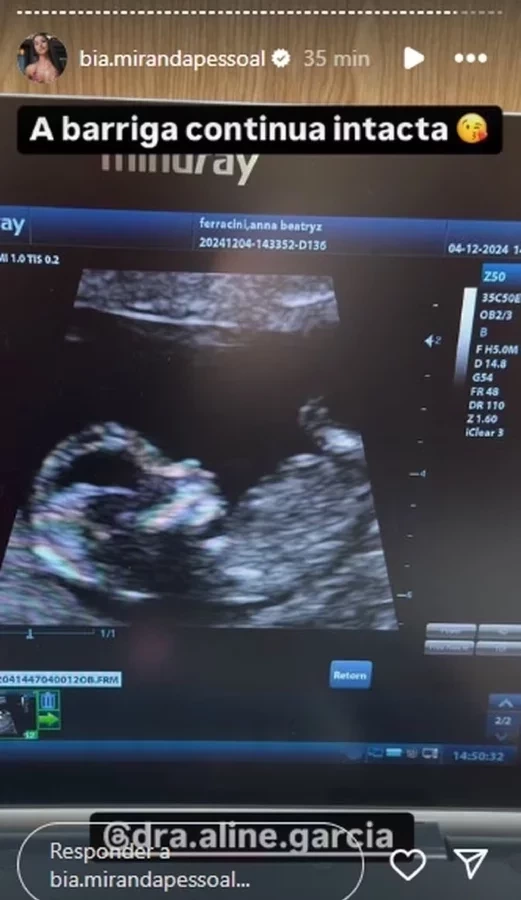

Bia Miranda segue ostentando sua barriga chapada, e mais uma vez a influenciadora foi acusada de mentir sobre estar grávida do influenciador Samuel Sant'Anna, conhecido como Gato Preto. Mas, a neta de Gretchen decidiu rebater os comentários nesta quarta-feira (4), compartilhando a imagem de um ultrassom.

Bia compartilhou alguns comentários que diziam que ela não estava grávida de verdade, por conta da barriga que não estava crescendo. "Gente, a barriga nunca cresce (risos), já faz uns meses que ela está grávida e nada de crescer", disse uma pessoa. "Com lipo, até eu fico transparente", provocou outra. "Duvido que ela esteja grávida", acrescentou mais uma. Em seguida, ela rebateu as críticas afirmando que nunca fez lipo: "Nunca fiz lipo. Doze semanas e quatro dias com a barriga chapadinha."